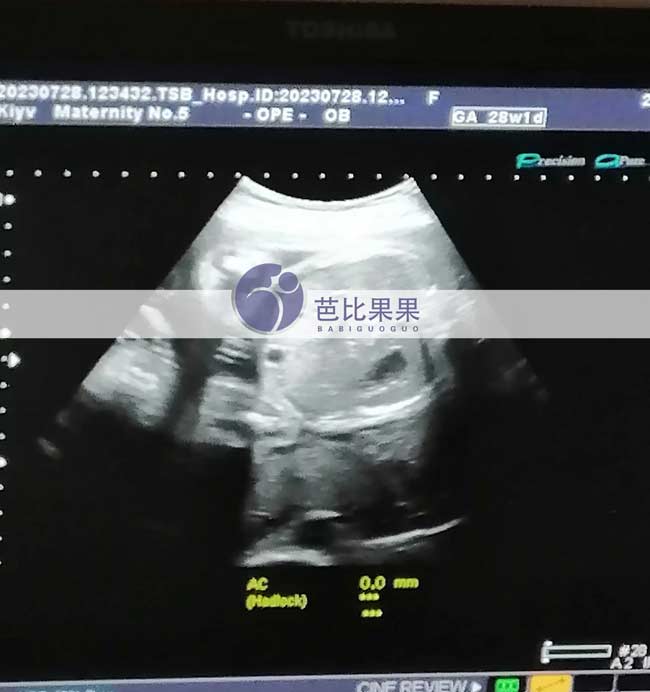

昆明Z女士家的乌克兰试管妈妈按时来医院28周的B超孕检

昆明Z女士家的乌克兰试管妈妈按时来医院做了28周的B超孕检,得知胎儿发育得很好,妈妈露出开心的笑容